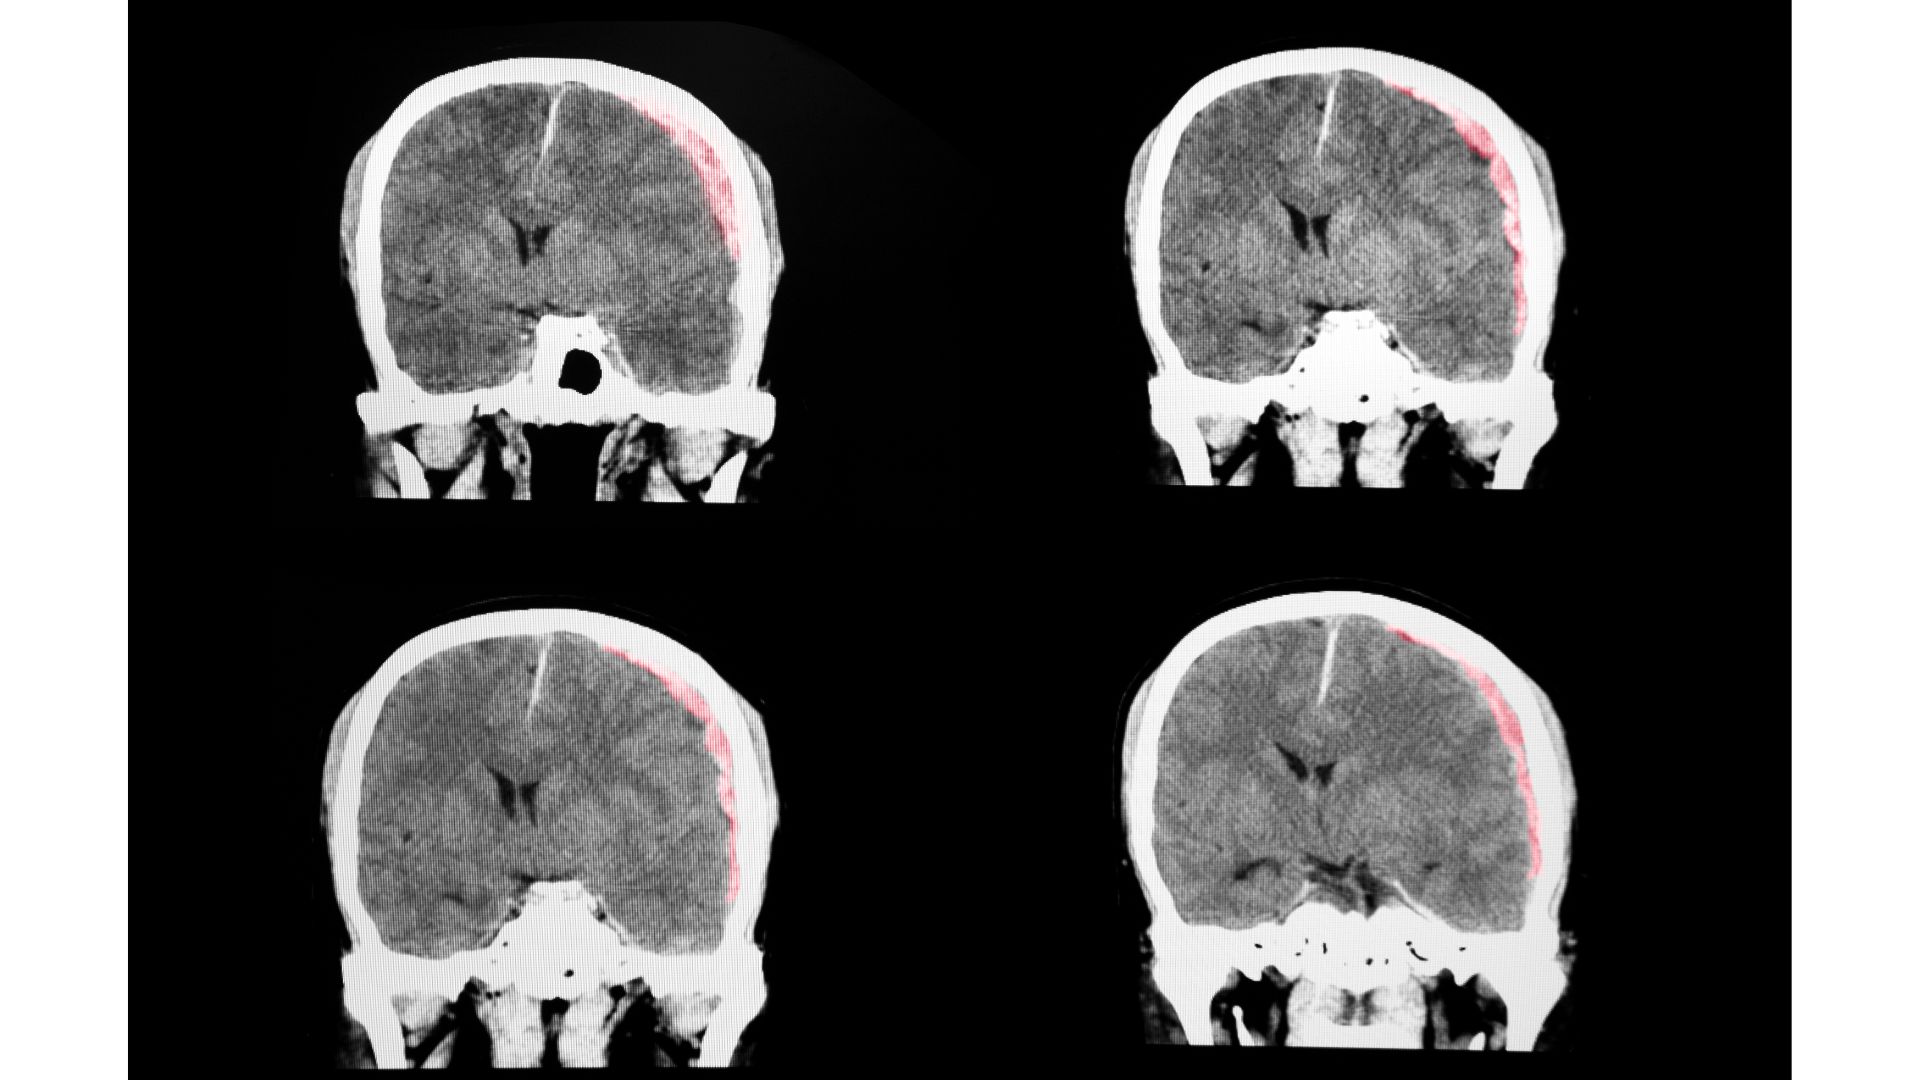

Brain and spinal cord injuries are some of the most critical, devastating injuries that can occur in an accident.

In many cases, brain and spinal cord injuries are quite apparent and require emergency medical treatment.

However, this is not always what occurs after an accident. In some cases, the injuries are mild to moderate and can take time to manifest. If an accident victim doesn’t appear hurt right away, that does not mean that he or she is completely uninjured.